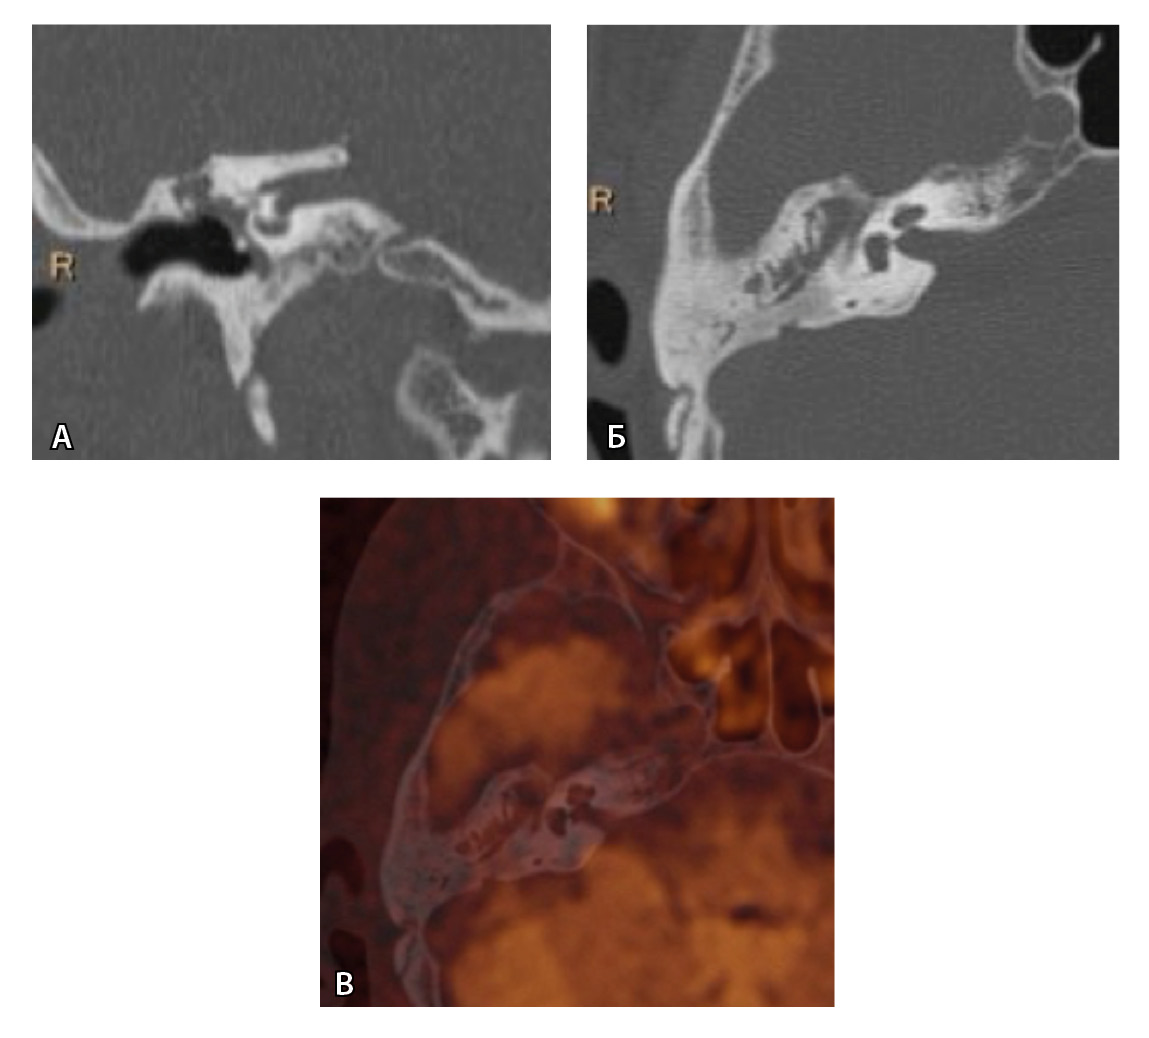

Рис. 4. При компьютерной томографии (КТ) визуализируются признаки хронического гнойного среднего отита справа. Наблюдаются латерализация косточек среднего уха и узурация их по имедиальной поверхности на уровне эпитимпанума (тело наковальни и головка молоточка) – классические КТ-признаки холестеатомы натянутой части барабанной перепонки (А, Б). Однако по данным магнитно-резонансной томографии (В) и в последующем при оперативном лечении холестеатома не подтверждена